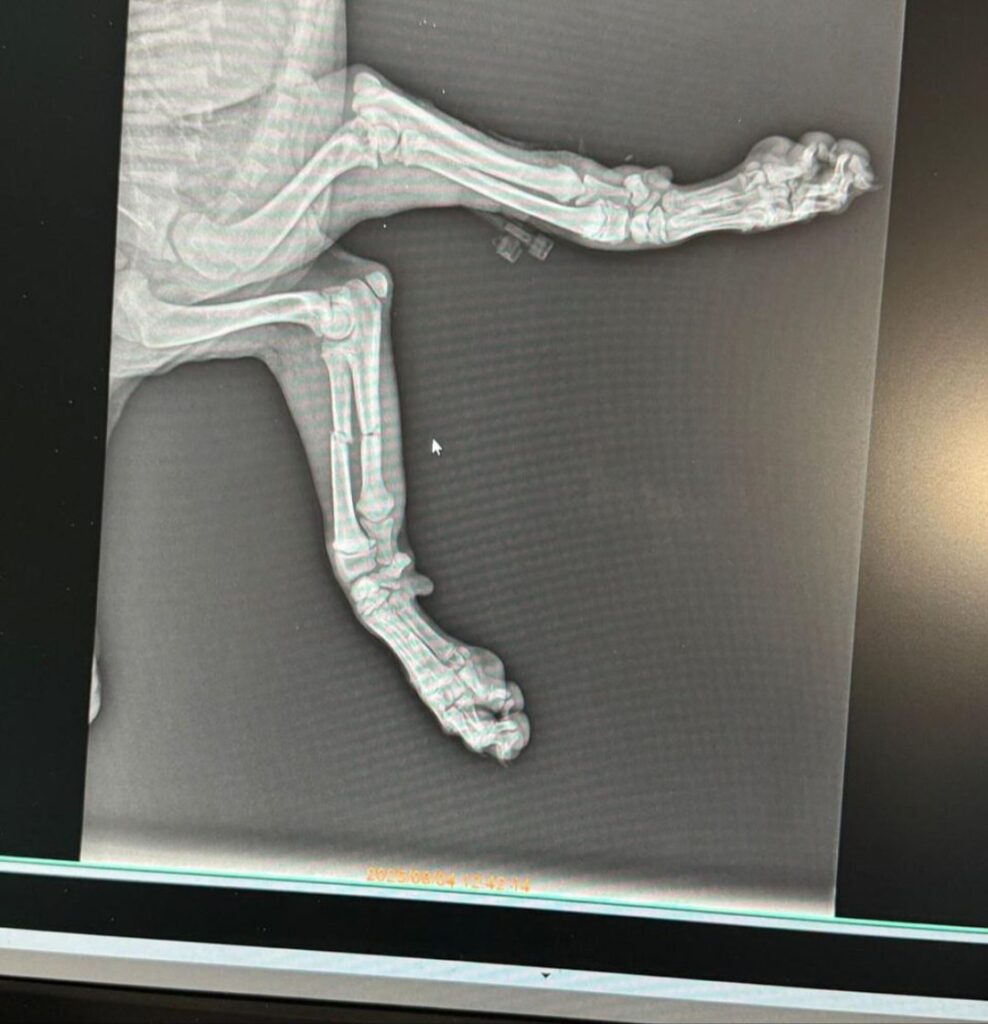

Hope got adopted in UK! Darling Hope, I will never forget the day I found you, how you were crying in pain and how my heart got destroyed! I promised you during the car ride I will never let you suffer again! We had to amputate your leg, but you were strong and full of will during those long two months at clinic. Your vet bill was more than 1000 EUR and we still did it for you cause you deserve it! Next battle was to find you a home! And we did it! We paid and additional 550 EUR for your UK transport. Thank you @pet_care_sarande for amazing work with amputation, thank you Jonida for hosting Hope for a few months, thank you Nadia for finding home in the UK! Hope was delivered to home address in UK! Hope, my baby, I hope I see you smiling and running those green fields all your life. You deserve better than here and you got it! I love you and I will miss you!